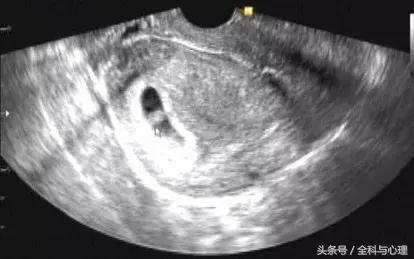

先兆流产是指28周前的宫内怀孕,出现少量阴道流血(不止红色才是出血,黑色、褐色的也算)、轻度下腹痛或者腰背酸痛等情况,宫口没有扩张。

从这个角度来说,先兆流产的病人来了医院,必须先做一件事:排除宫外孕和葡萄胎!只有明确是宫内怀孕,才能保胎。

早孕期经常会遇到B超查的胚囊小于实际停经时间的,我们不能轻易认定胚胎停育。这类情况可以给1-2周时间随访血hcg和B超,有先兆流产表现的,也可以同时保胎。

保胎过程可以随访B超,看得到胚胎的情况,是直接的判断标准。如果胚胎按规律生长,长出胚芽、原始心管搏动等,同时临床上的出血和腹痛也消失,那么保胎就可以算成功了。